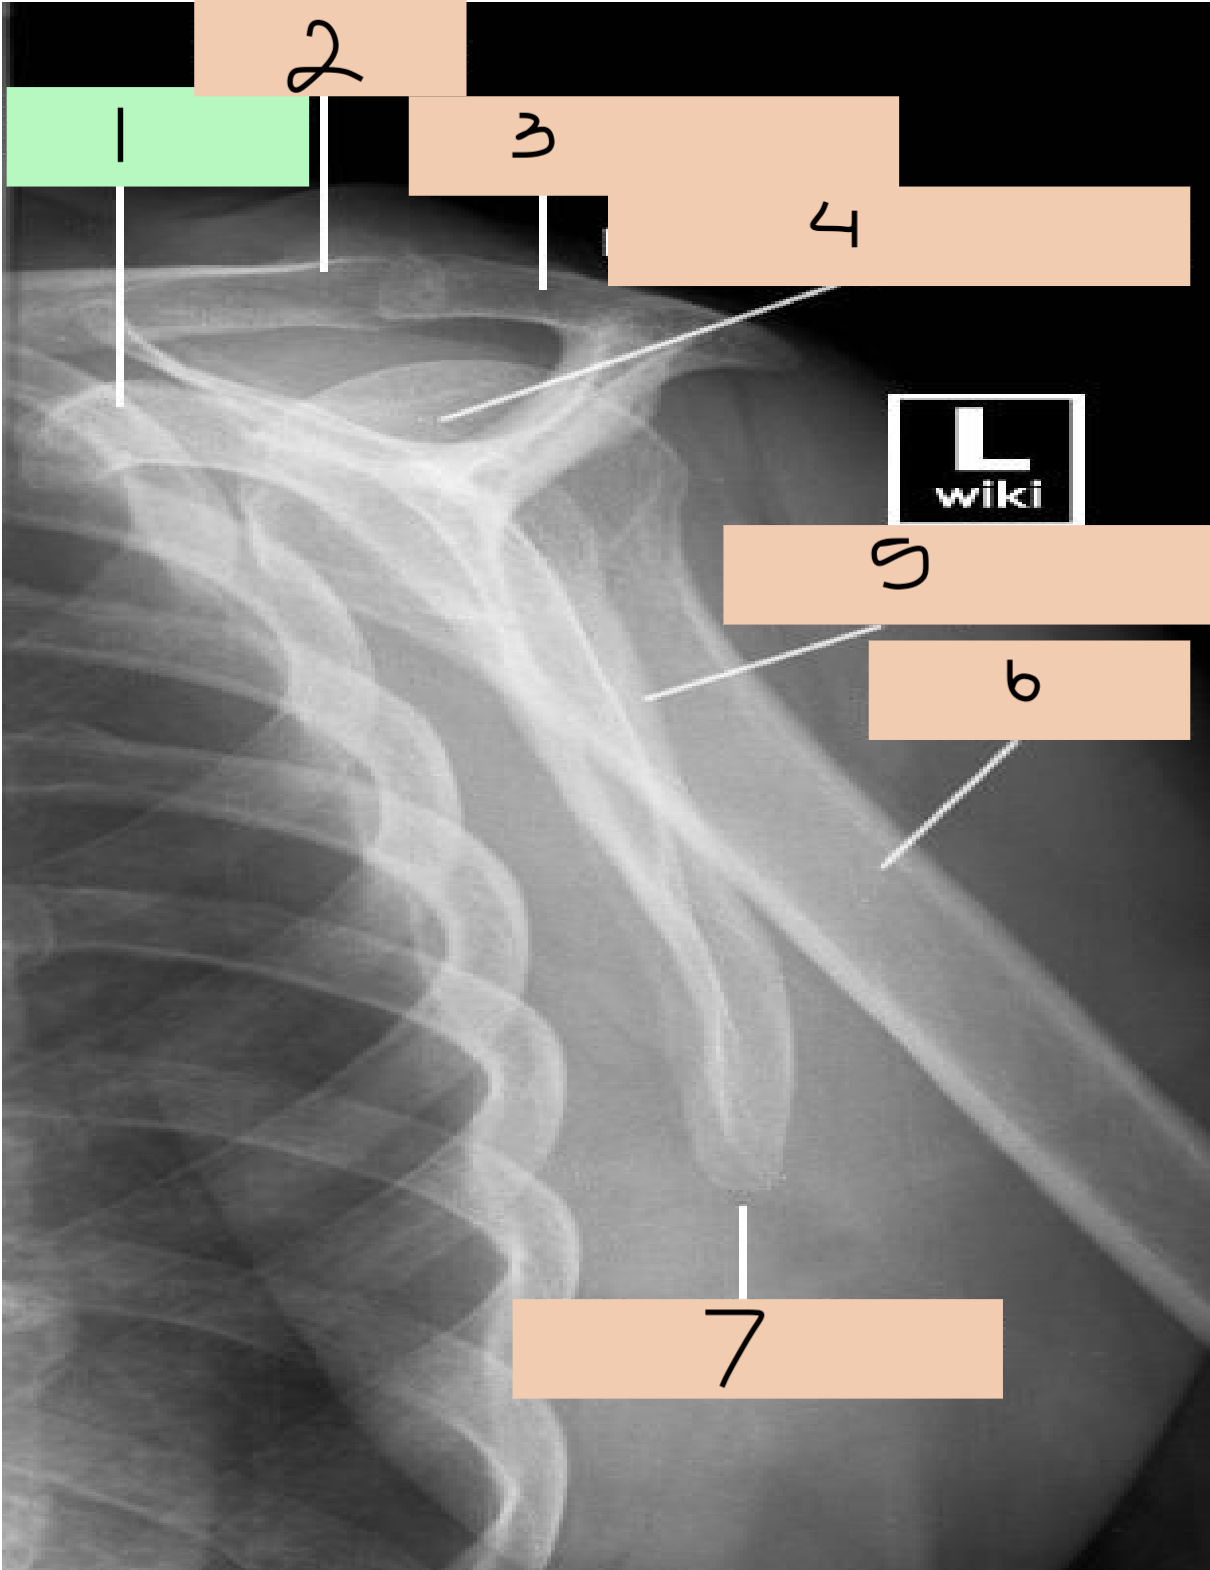

1

1st rib

2

clavicle

3

sternoclavicular joint

4

medial border scapula

5

inferior angle scapula

6

superior angle scapula

7

superior border scapula

8

coracoid process

9

glenoid fossa

10

lateral border scapula

12

acromioclavicular joint

13

acromion process

14

head of humerus

15

anatomical neck

16

greater tubercle

17

intertubercular groove

18

lesser tubercle

19

surgical neck